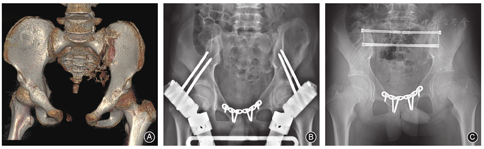

随着临床治疗水平的提高,尤其是机器人支援手术的开展,髋臼骨折的微创治疗也取得了相应的进步。然而,由于受到难以完全实现"骨折闭合复位"的限制,机器人辅助经皮螺钉内固定目前仅适用于治疗无移位或移位轻微(≤2 mm)的潜在不稳定型髋臼骨折。

手术适应证主要包括髋臼横行、"T"形、高位前柱及耻骨上支骨折等。

前柱位于髋臼上方与耻骨联合之间,由表面皮质骨和内部松质骨组成。螺钉通道可理解为居于骨性安全边界内的模拟柱状体结构,其狭窄处分别位于髂耻隆起的两侧、闭孔顶点及髋臼内侧壁。螺钉距离髋关节越近,则固定强度越大。术中应根据骨盆类型(男人型、女人型、扁平型、类人猿型、均小型等)对螺钉入点及行进方向作出调整。

机器人辅助髋臼前柱螺钉置入时,患者采取仰卧位或侧卧位,按术前规划进行钉道准备。术中借助骨盆入口、髂骨入口及闭孔出口位的双平面影像切换,引导螺钉通过骨折端。固定方式:(1)顺行螺钉固定:是耻骨上支NakataniⅢ型骨折的最佳适应证。入钉点范围大,位于髋臼上方3~4 cm及臀中肌附着处。术中显露困难,不易改变导针及螺钉方向,目前最适合机器人辅助定位。(2)逆行螺钉固定:常用于治疗NakataniⅠ、Ⅱ型骨折。入钉点范围小,位于耻骨结节的前下方(男女略有不同),可在体表扪及。术中便于确认导针螺钉方向,目前不适采用机器人辅助固定。

基于循证依据支撑的"迭代手术(technical iteration)方式"。通过机器人技术的功能延伸进一步扩大其应用范围。可用于处理:儿童及青少年骨盆损伤(图5)、老年骨盆骨折的螺钉通道强化及骨折端注射植骨材料填充(图6)、骶骨骨折伴腰骶结合部损伤或创伤性脊柱骨盆分离的经皮髂腰三角或髂腰固定(图7)。